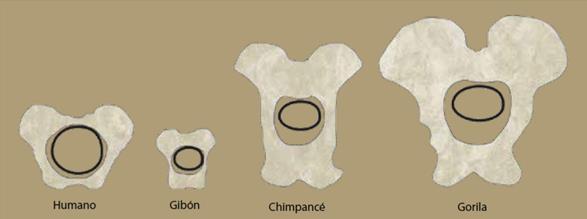

La pelvis humana está comprimida en el plano horizontal en comparación con la de un chimpancé, en el que la pelvis es estrecha horizontalmente, pero muy elongada en el plano vertical (figura 2). La compresión de la pelvis en los humanos, con los bordes frontal y posterior en el mismo plano horizontal, es responsable de la restricción del canal pélvico. Las hojas iliacas cortas y gruesas de la pelvis humana están en posición lateral sobre las articulaciones, reposicionando los glúteos medio y menor y cambiando su función.

Figura 2 Pelvis humana (der) comparada con la de un chimpancé (izq). Nótense la forma circular y dimensiones estrechasdel canal en la pelvis humana.

Los miembros más primitivos de nuestro linaje, cuyos restos fosilizados están suficientemente completos para poder analizar la pelvis en forma general, datan de aproximadamente 3 millones de años y han sido colocados en el género Australopithecus (AL288-1 [la pelvis de Lucy] de Hadar, Etiopía; Sts 14, de Sterkfontein, SudÁfrica) (figura 3)6. Los australopithecines eran bípedos completos y eficientes, pero poseían un cerebro de aproximadamente la cuarta parte del tamaño de el de un humano moderno (aproximadamente 400 ml comparado con cerebros humanos modernos de entre 1,300 y 1,400 ml). Este género está limitado a África y fue el antecesor directo del género Homo y eventualmente de los humanos modernos.

Probablemente las características del dilema obstétrico aparecieron alrededor de la época del origen del género Homo, hace aproximadamente 2.5-2.0 millones de años, cuando el tamaño del cerebro casi se triplicó, el tamaño del cuerpo aumentó enormemente y la pelvis empezó a expandirse en la dimensión anteroposterior, tomando una forma humana más moderna (figura 10). Aunque no hay un acuerdo general sobre qué parte del paquete de características obstétricas evolucionó en ese tiempo, la combinación de alteraciones en la morfología pélvica con cerebros agrandados indica que ya había empezado a emerger el patrón de nacimiento del neonato humano. Hace 300,000 años el tamaño del cerebro y la morfología de la pelvis eran esencialmente idénticos a los humanos modernos y se supone que el mecanismo del nacimiento también había tomado su forma moderna.

Figura 10 Relación entre las dimensiones de la pelvis materna y el cráneo del humano en varios simios, gibón, chimpancé y gorila.